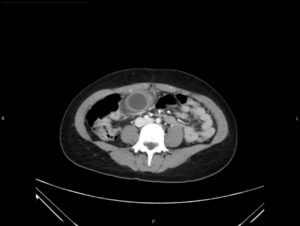

Hydropic Gallbladder. CT Axial, Unannotated. JETem 2025

Hydropic Gallbladder. CT Axial Unannotated. JETem 2025